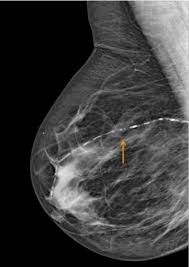

Plos One Prevalence Of Coronary Artery Disease Evaluated By Coronary Ct Angiography In Women With Mammographically Detected Breast Arterial Calcifications

Figure 2 From Prevalence Of Coronary Artery Disease Evaluated By Coronary Ct Angiography In Women With Mammographically Detected Breast Arterial Calcifications Semantic Scholar

Do Breast Arterial Calcifications On Mammography Predict Elevated Risk Of Coronary Artery Disease European Journal Of Radiology

Vascular Calcifications Seen On Mammography An Independent Factor Indicating Coronary Artery Disease

Mammary Artery Calcification A Useful Marker For Coronary Artery Disease